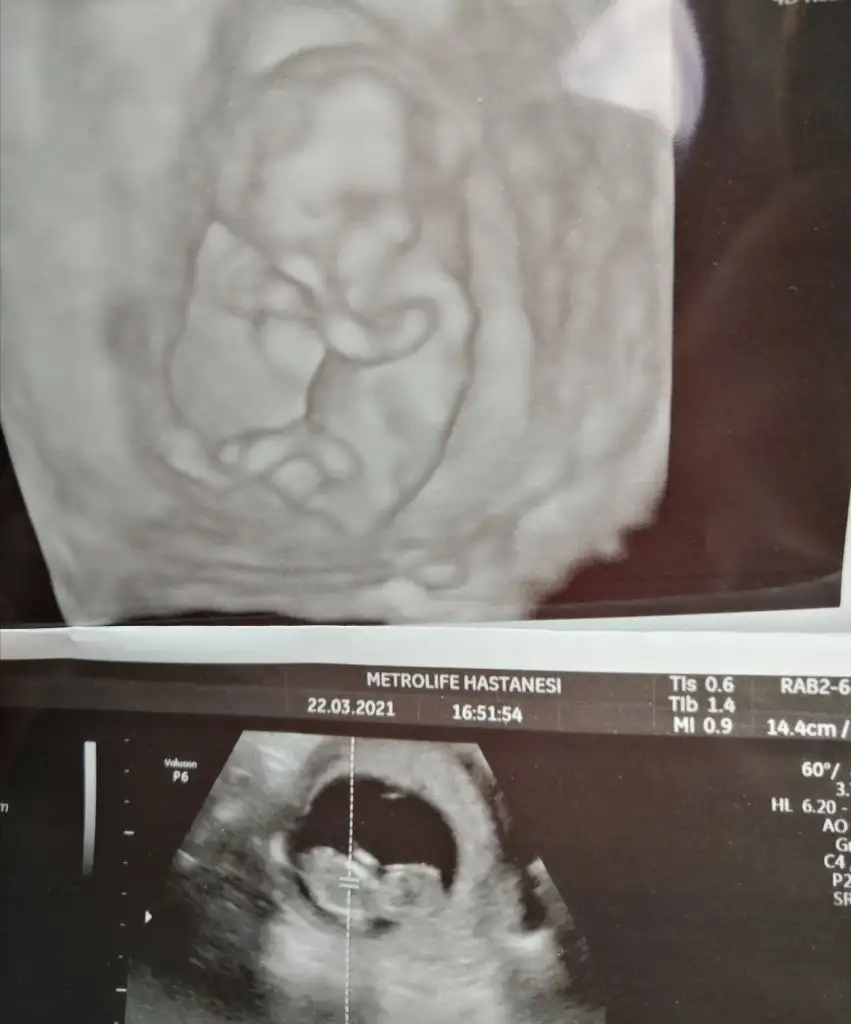

Merhaba 11+4de size usg atmıştım kız gibi demistiniz şimdi 14+5 atıyorum tekrar yorumlarmısiniz hala söylemedi doktorErkek görünüyor

Ay ben ikra kadar anlamam ama kız gibi geldi yaMerhaba 11+4de size usg atmıştım kız gibi demistiniz şimdi 14+5 atıyorum tekrar yorumlarmısiniz hala söylemedi doktor

11+4 de kız demiştim ama 14+5 de artık organı oluşmuş oluyor bakalım hayırlısı olsun tipi kız gibiMerhaba 11+4de size usg atmıştım kız gibi demistiniz şimdi 14+5 atıyorum tekrar yorumlarmısiniz hala söylemedi doktor

Evet net kız görünüyorMerhaba arkadaşlar 12+4 tahminler var mı dr um %80 Kiz dedi

Kız sanki